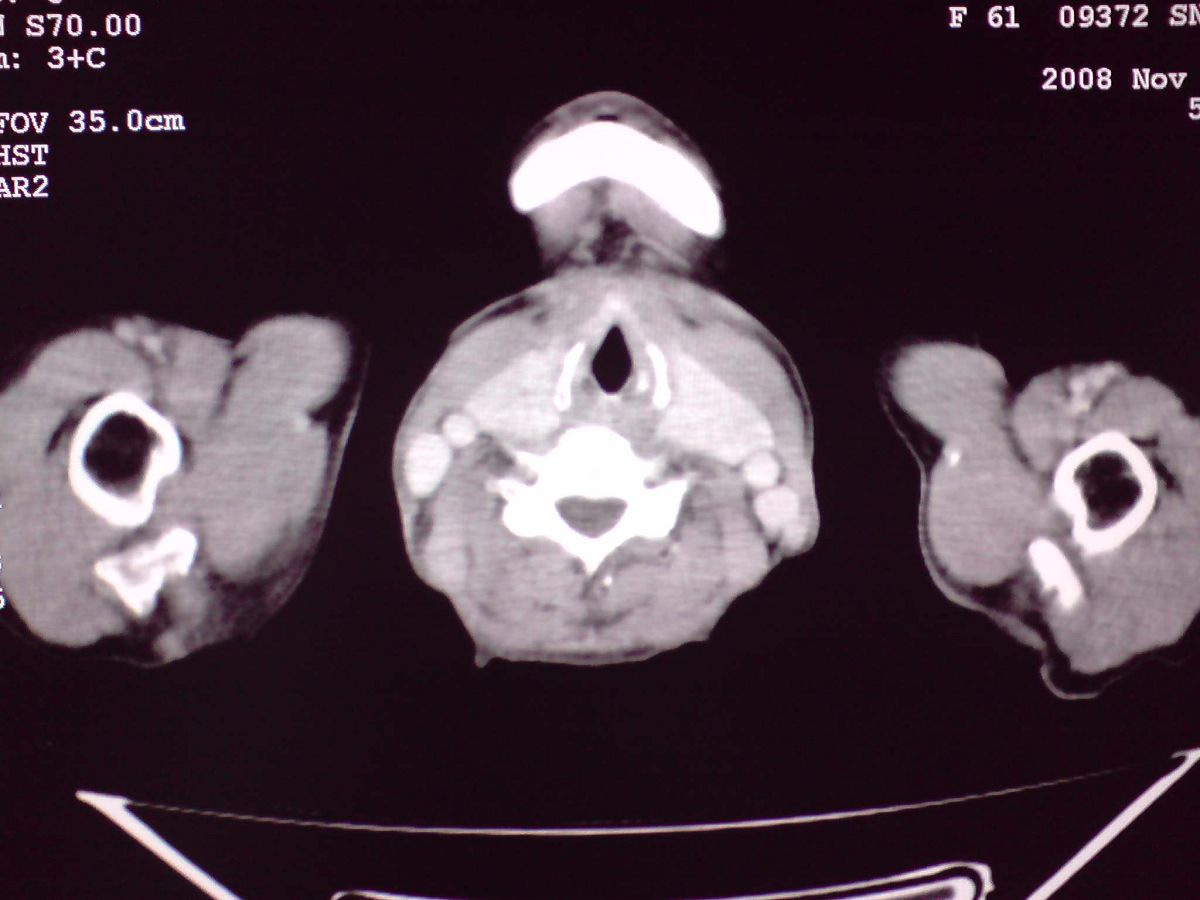

患者女性,65岁,无明显不适,甲状腺功能无异常

结节状甲状腺肿,部分突入胸腔,形成胸内甲状腺

胸内甲状腺伴结节性甲状腺肿!因病灶明显钙化很难排除:甲状腺癌可能性!建议穿刺活检!

双侧甲状腺肿大,向下部分突入胸腔,双侧甲状腺内密度不均,可见结节状低密度影,并见散在斑点状钙化,增强后病灶实性部分强化明显,气管受压稍变窄左移。

考虑:双侧甲状腺腺瘤可能,不除外甲状腺癌。

甲状腺左右叶增大,并向下突入胸腔内,其内可见多发条片状钙化影及囊性低密度影,邻近组织及血管无浸润、包埋征像,双侧结节性甲状腺肿伴右侧甲状腺腺瘤形成可能性大,甲状腺癌待排;因病人就要手术,期待结果。